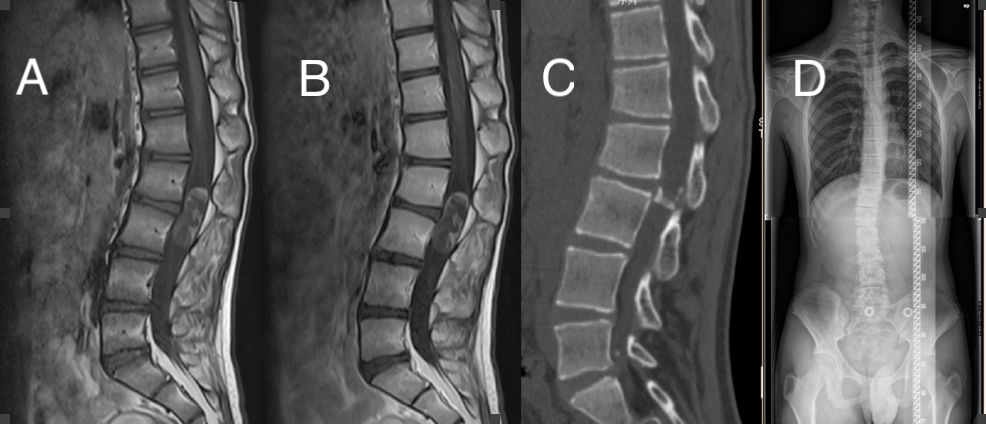

腰椎增强MRI提示:腰2-3椎体水平椎管内见椭圆形病灶,大小约40*15mm,以长T1长T2信号为主,内信号不均,见稍短T1稍短T2信号,增强扫描未见确切强化。CT示:腰2-3椎体水平椎管内见椭圆形大小约40*15mm低密度影,内密度不均,病灶内及边缘见弧形及斑点状钙化。全脊柱摄片提示:脊柱胸段向左侧凸,腰段向右侧凸。Cobb角为14°(图1)。

图1. A:MRI T1序列, B:MRI T1增强序列, C:CT矢状位,D:全脊柱摄片。